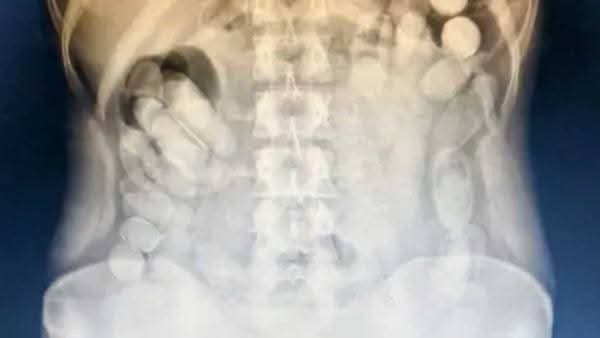

Allí, una radiografía confirmó la presencia de múltiples cápsulas en su abdomen.Horas después, la mujer evacuó un total de 106 cápsulas.